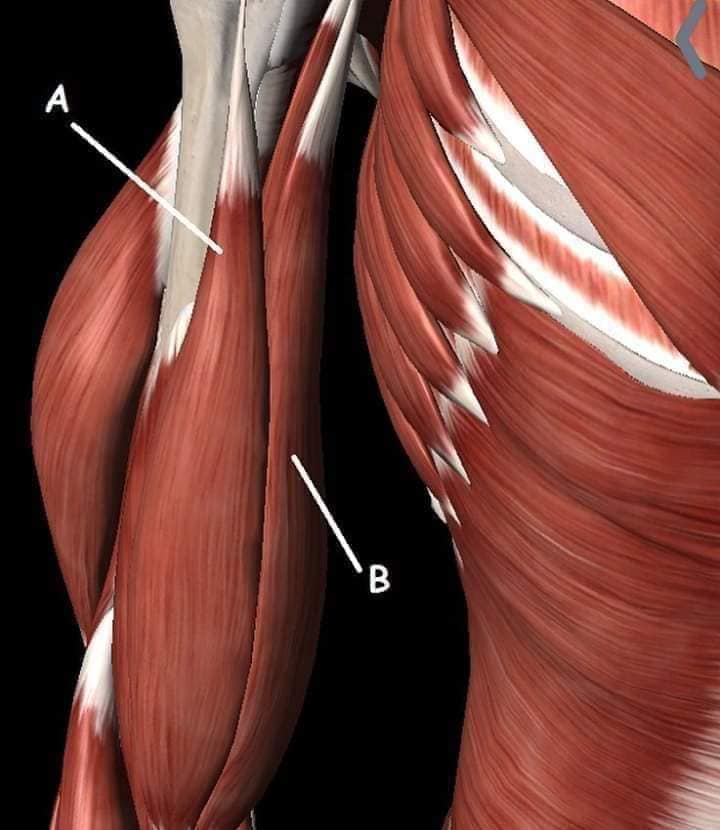

М'язи, що ведуть лопатку до хребта: Широкий м'яз спини: великий м'яз, що розташований в нижній частині спини. Він відповідає за рухи плечей і лопаток, а також за розширення верхньої частини тулуба.